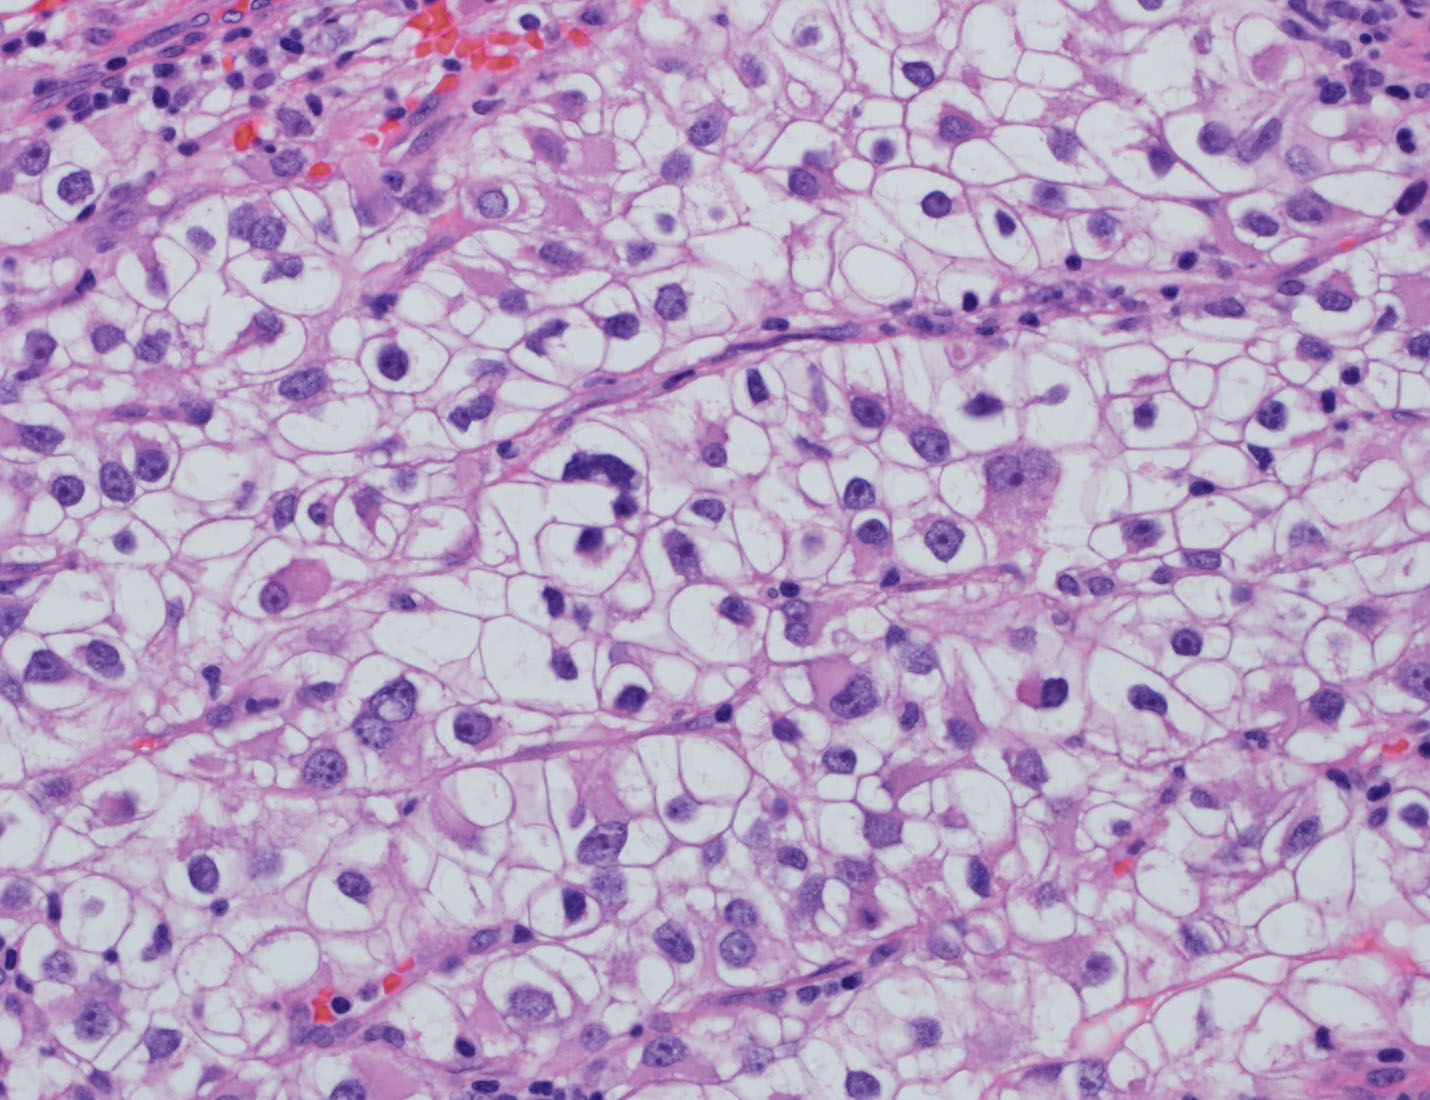

Consensus grade: Clear cell RCC

Show diagnosis by expert panel members| User | Diagnosis | Difficulty | Comment |

|---|---|---|---|

| Pathologist 1 | Clear cell RCC | Typical | |

| Pathologist 2 | Other | Not typical |

Probably a clear cell |

| Pathologist 3 | Clear cell RCC | Typical | |

| Pathologist 4 | Clear cell RCC | Typical |

Nucleolar grade 3 |

| Pathologist 5 | Clear cell RCC | Typical |

High grade |

| Pathologist 6 | Clear cell RCC | Typical | |

| Pathologist 7 | Clear cell RCC | Typical |

Rhabdoid |

| Pathologist 8 | Clear cell RCC | Typical | |

| Pathologist 9 | Clear cell RCC | Typical | |

| Pathologist 10 | Clear cell RCC | Not typical | |

| Pathologist 11 | Clear cell RCC | Typical | |

| Pathologist 12 | Clear cell RCC | Typical | |

| Pathologist 13 | Clear cell RCC | Typical | |

| Pathologist 14 | Clear cell RCC | Typical | |

| Pathologist 15 | Clear cell RCC | Typical | |

| Pathologist 16 | Clear cell RCC | Typical |

low power ? |

| Pathologist 17 | Clear cell RCC | Typical |